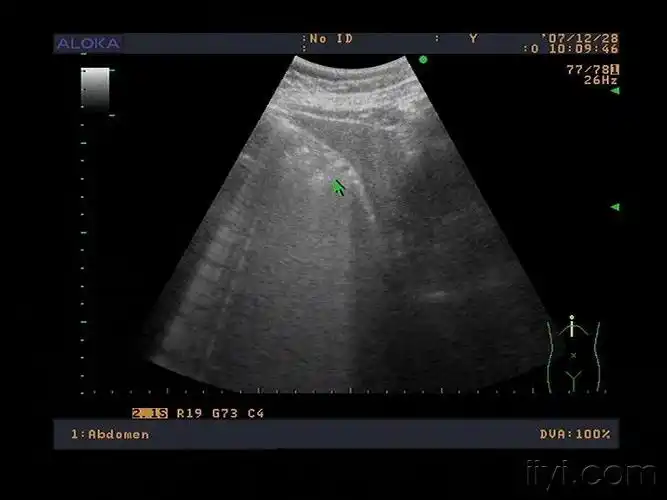

肿大的胆囊张力很高,胆囊壁增厚,囊内胆汁透声不佳,有结石,有胆泥沉积